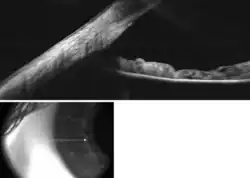

![]() Enlarged general view of the iridial angle. (When enlarged, visible with older label of 'trabecular tissue') | |

The trabecular meshwork is an area of tissue in the eye located around the base of the cornea, near the ciliary body, and is responsible for draining the aqueous humor from the eye via the anterior chamber (the chamber on the front of the eye covered by the cornea).